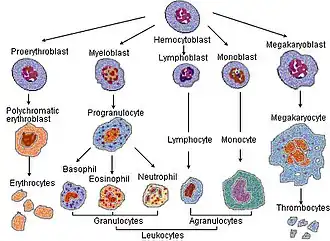

Blood cell lineage

Blood cell lineage -

_diagram_en.svg.png) More complete lineages

More complete lineages